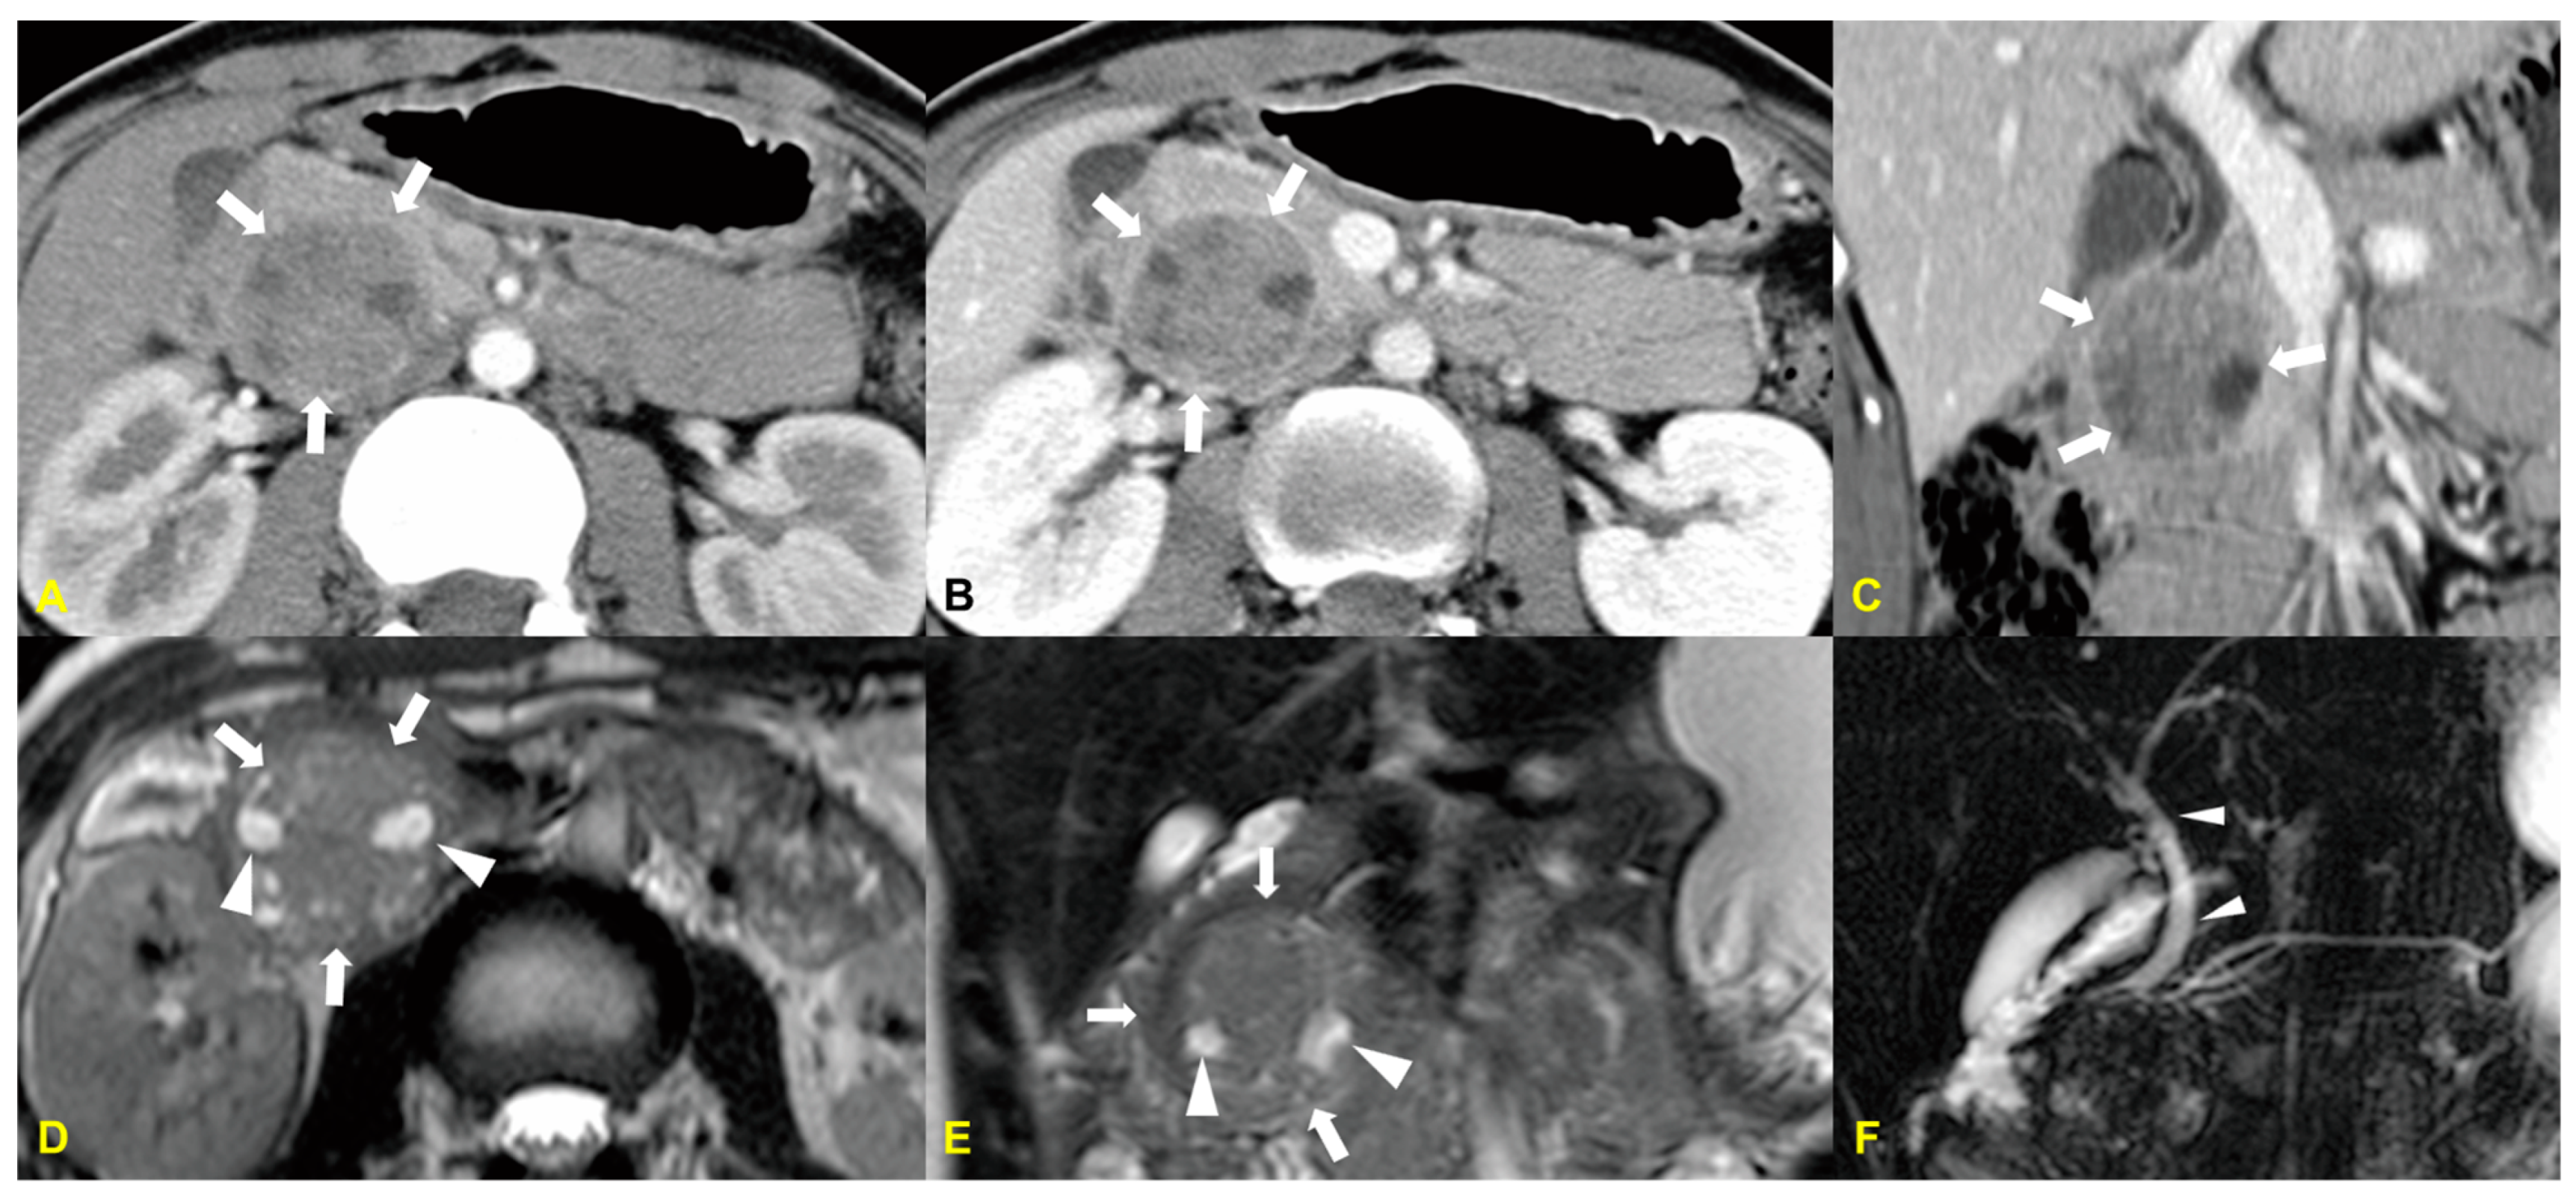

6. Primary Pancreatic Lymphoma (PPL)

6.1. Imaging Finding

6.2. Differential Diagnosis

| Primary lymphoma | Localized type: well defined mass with poor enhancement/Low-to-intermediate SI on T2WI |

| Diffuse infiltrating type: hypointense enlarged pancreas on T1- and T2WI | |